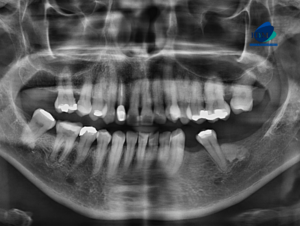

Paciente femenina acude a la sede de IDM- Miraflores para una tomografía computarizada para la evaluación de terceras molares. A la evaluación de la radiografía